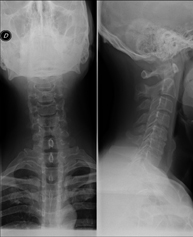

- Cervical spine X-ray

This technique uses X-ray rendered imaging for examining the cervical spine. Indicated for: trauma, cervical contracture, joint pain.

This technique uses X-ray rendered imaging for examining the cervical spine. Indicated for: trauma, cervical pain.